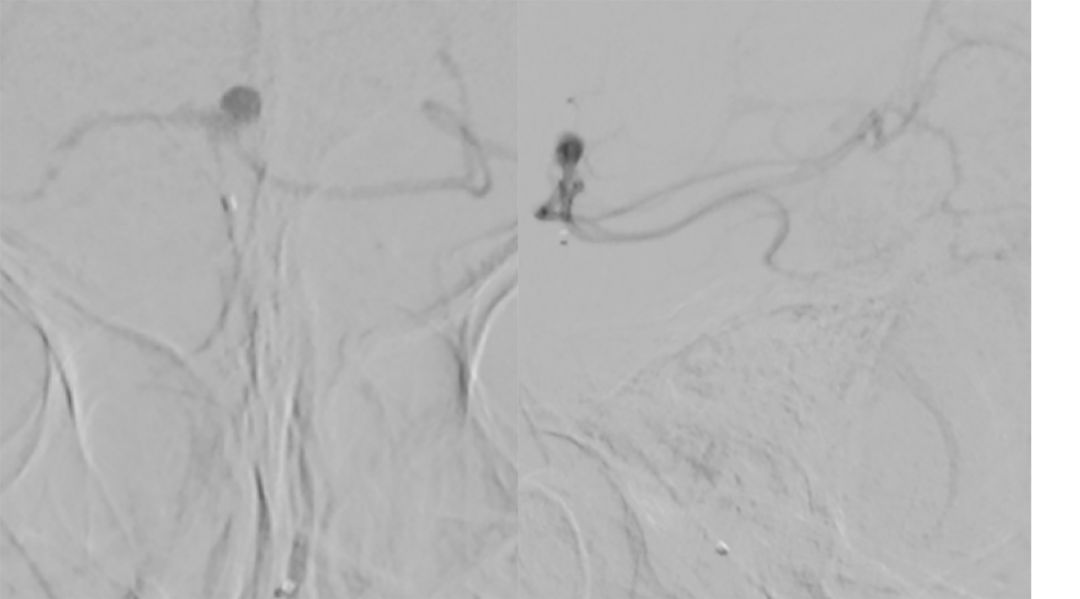

基底动脉进行三维血管重建:基底动脉有较粗和较细的2个管腔,左侧小脑上动脉瘤大小约2.3*2.1 mm(图9)。

图9

进行上述三次微量造影均可见双侧大脑后动脉显影,以及结合基底动脉三维重建图像,故判断基底动脉属于开窗,而非夹层。由于载瘤动脉较细,拟行单微管动脉瘤栓塞术。

5. 调整至合适的工作角度后,路径图引导下,Synchro(0.014,200 cm)微导丝携Echelon-10微导管超选进入左侧小脑上动脉瘤(图10微导丝到位,图11微导管到位)。

图10 微导丝到位 图11 微导管到位